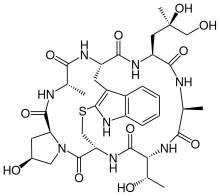

Chemical structures

Phalloidin

Phalloidin Prophalloin